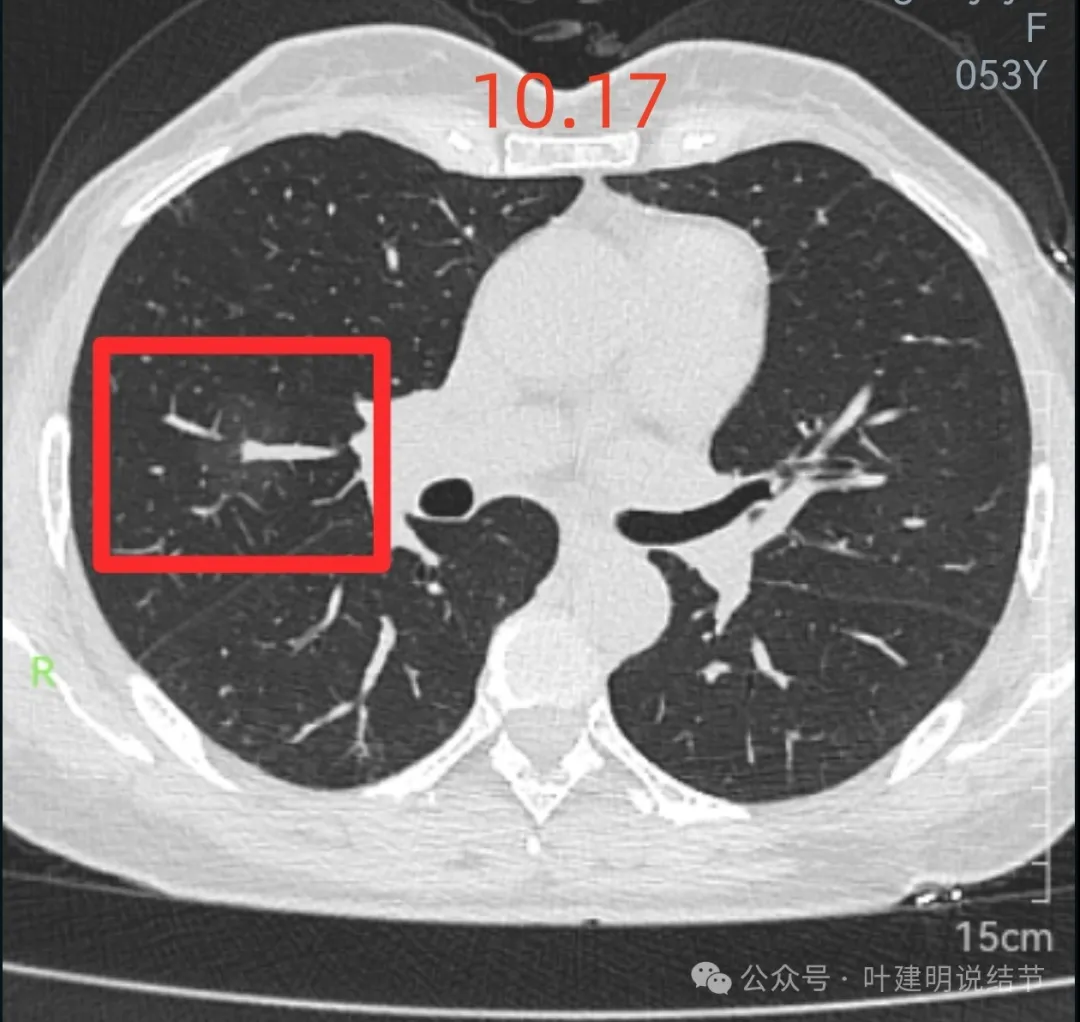

先来看2024年10月16日的影像:

右肺很淡的磨玻璃阴影,伴进入的血管异常增粗,整体轮廓尚显清楚。

左下小片状模糊影,轮廓与边界欠清。

左下叶混合密度结节,边缘有淡的磨玻璃影,瘤肺边界欠清,实性成分明显,略偏散。

右下叶以及左下叶实性结节,缺乏膨胀性,没有收缩力,紧贴胸壁或膈肌无牵拉凹陷。

再来看周教授认为4B类的右上后段病灶连续层面影像信息:

病灶出现,轮廓不清,瘤肺边界模糊,有血管穿行,血管有异常增粗。

血管壁有异常密度增高,病灶混合密度,轮廓总体在此层较清,但瘤肺边界不清。

病灶偏实性部分不密实,磨玻璃部分过淡且模糊。

边缘有毛刺,但不够锐利;外周磨玻璃成分密度过淡且界限不清;实性部分也显得不致密;与叶间裂距离近但没有任何牵拉影响。

实性成分在灶内看,也是界限不清,磨玻璃部分淡而糊。

整体感觉像病灶中间偏实性些的成分伴外周晕征。

边缘区域离叶间裂更近,仍无牵拉。

几乎贴着叶间裂了,仍无任何牵拉影响。

病灶密度边缘部分也不均,离叶间裂近而没有影响。

上图病灶已经贴着叶间裂,但仍显示是平直的,没有任何牵拉影响。

矢状位上看,病灶虽整体轮廓较清,但瘤肺边界显模糊,整体不致密。

冠状位上看病灶有实性成分,实性成分缺乏收缩力,外围是淡磨玻璃成分,瘤肺边界欠清,贴着叶裂没有影响。

从连续层面以及影像细节上看,这个病灶就不可能是恶性的!短期内出现,混合密度而瘤肺边界不清,整体缺乏收缩力也无膨胀性,灶内实性成分不致密且磨玻璃成分过淡,灶内血管有异常增粗与密度过高,又是两肺多发病灶。这所有的表现与病情发展都与感染性病变契合,周围淡磨就是炎症水肿的关系,血管异常就是管壁有炎症的关系,多发就是感染(致病因素)影响两肺的关系。怎么可能是恶性?